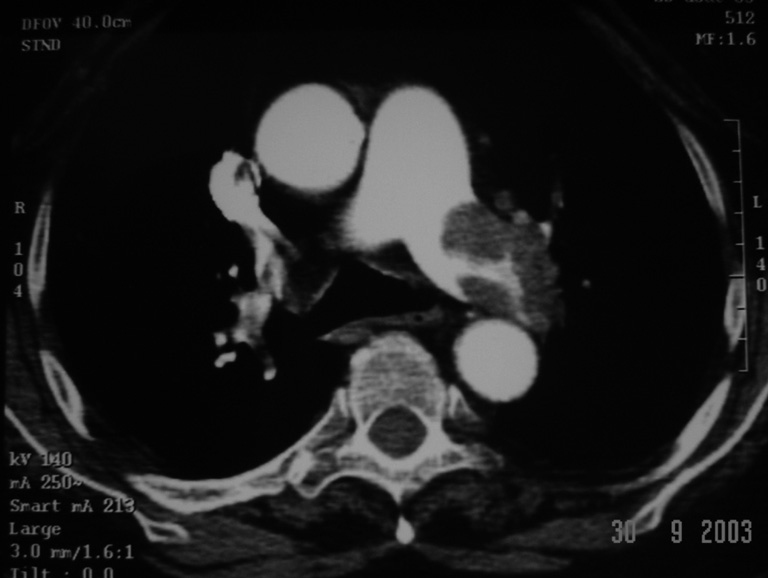

Cas clinique : Figure 1